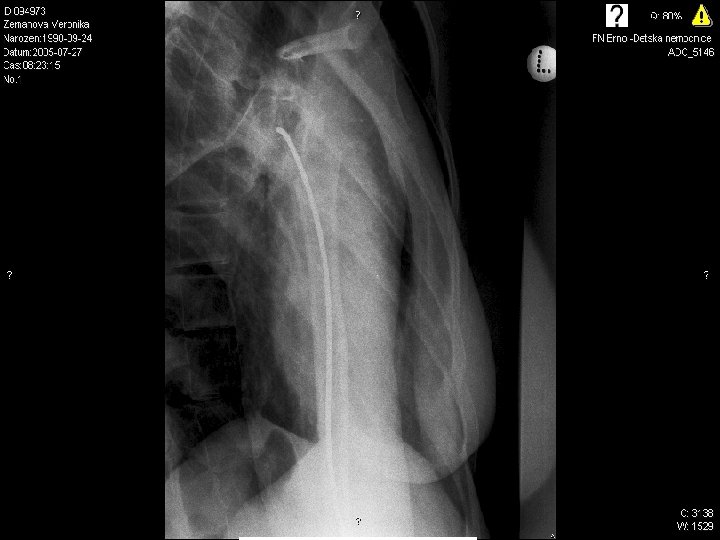

1

2

3

4

5

6

7

8

9

10 17. 4. 2005

Radiodiagnostic test conclusions

10